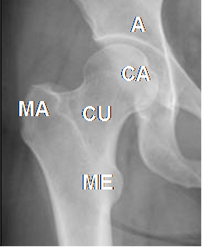

Fig 10. Estructuras óseas en la cadera.

A: Acetábulo. CA: Cabeza femoral. CU: Cuello femoral. MA: Trocánter mayor. ME: Trocánter menor.